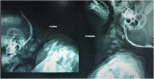

Case presentation: We report a case of a 6-month-old female, diagnosed with Larsen syndrome. She presented with progressive upper and lower limbs spasticity, flexed neck, and bilateral resistant developmental dysplasia of the hip. A C3 corpectomy with iliac crest allograft was done and 2. 7 plates with screws in C2 and C4 were placed. An abduction brace (Pavlik harness) was used for 3 months after the surgery to prevent early collapse. V体育安卓版.